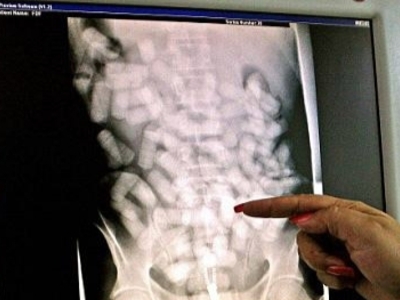

The man tried to smuggle drugs in his intestines. These were hidden in the condoms he swallowed. But one condom broke and killed the man almost instantly.